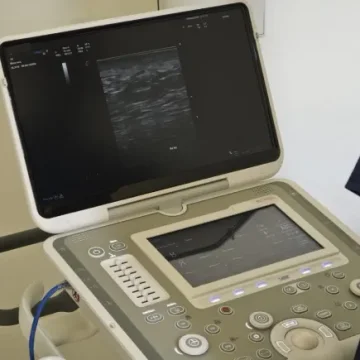

Análisis con ecografía

Se realiza un análisis complementario con una fiabilidad del 99,99 %, que aporta una capa extra de seguridad y precisión quirúrgica en la planificación del procedimiento. Disponible por solo 90€ (opcional)